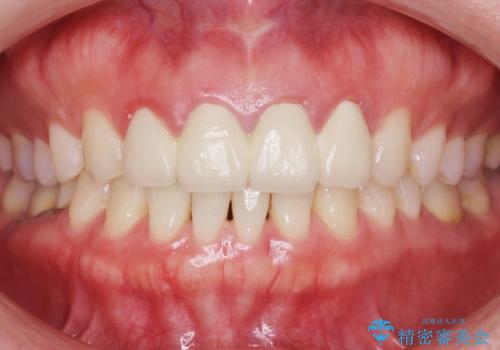

自然な仕上がりに大変喜んで頂けました。

単冠かつ適合の良いクラウンにより清掃性が良くなり、歯茎の腫れ・出血もなくなりました。

天然歯と見紛うほど自然なセラミッククラウンは、熟練した技工士さんの技術の賜物です。

クラウンの種類:ジルコニアオールセラミッククラウン エクセレント